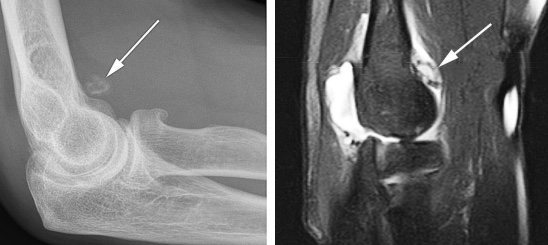

(Справа) На сагиттальной МРТ PDBИ определяется частичный отрыв сухожилия трехглавой мышцы с небольшим оторвавшимся костным отломком МРТ может быть информативна при оценке степени повреждения трехглавой мышцы. (Слева) На сагиттальной КТ с реформатированием можно видеть раздробление локтевого отростка после падения на локтевой сустав. Перелом открывается на суставную поверхность в нескольких местах.

3. МРТ при переломе локтевого отростка:

• Линия перелома лучше видна на сагиттальной и фронтальной Т1ВИ и Т2ВИ FS

• Стрессовое повреждение может определяться только по отеку костного мозга без линии перелома

• На МРТ можно не заметить небольшие переломы кончика

о МРТ для оценки целостности трехглавой мышцы

о МРТ: сагиттальная и осевая Т2ВИ для оценки перелома и целостности трехглавой мышцы